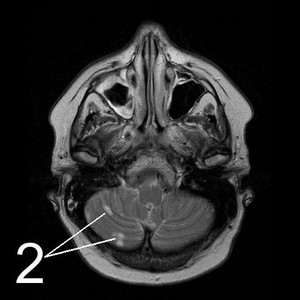

МР-томограммы мозга.1.     Киста после кровоизлияния в мозг2.    Кисты мозжечка после ишемического инсульта (закупорка мозговых артерий)3.     Кистозно-слипчивый арахноидит

Обследование и диагноз

МР-томография или КТ дадут однозначную информацию о наличии, размерах и расположении кисты. Отличить кисту от опухоли помогает исследование с внутривенным введением контраста: опухоль накапливает контраст, а киста – нет. Выполнить такое исследование Вы можете в Клинике Академии наук.

Чтобы избежать увеличения и появления новых кист, мы должны четко понимать и лечить первопричину их возникновения. Поэтому мы тщательно обследуем Вас на предмет нарушений кровообращения, инфекций, аутоиммунных заболеваний.